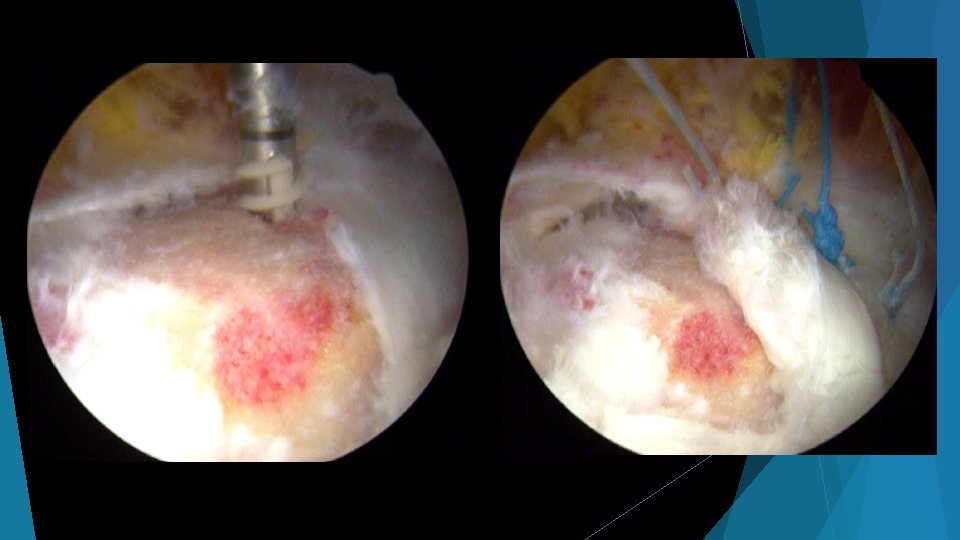

Abductor repair surgery